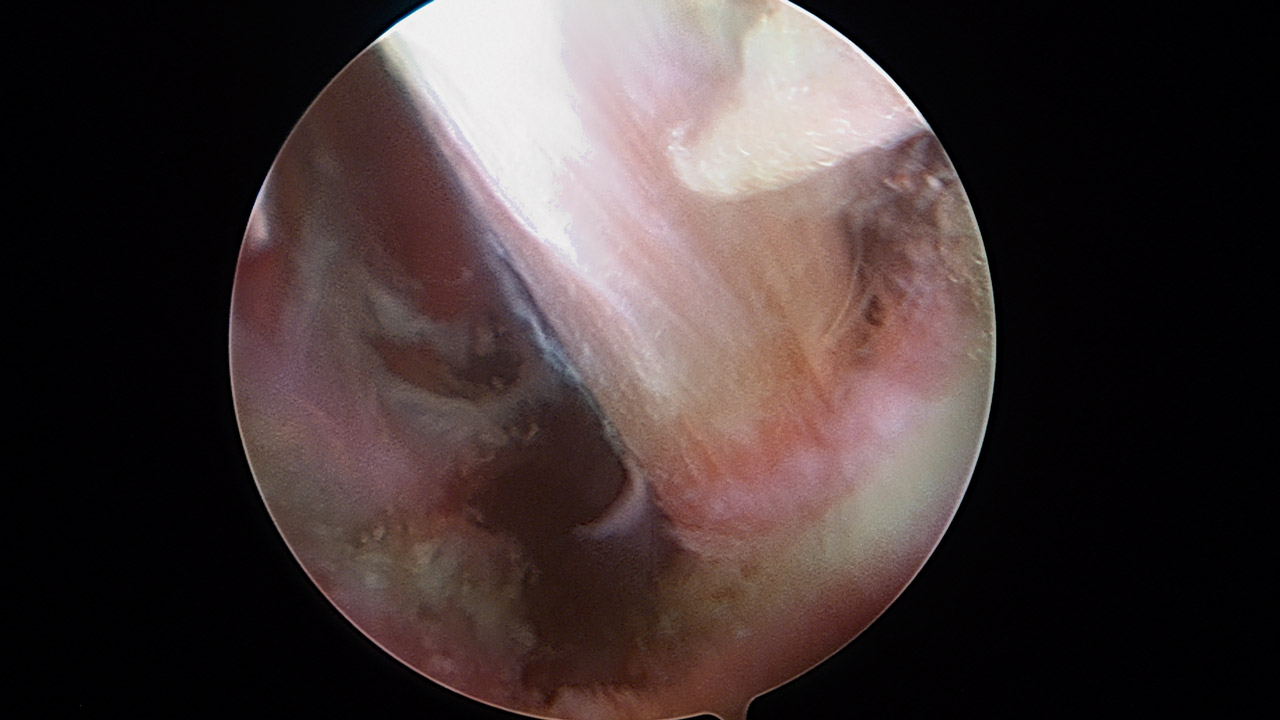

Presentamos una técnica quirúrgica artroscópica para los casos de inestabilidad traumática o atraumática de hombro, con hiperlaxitud multidireccional asociada, en los que hayan fracasado los tratamientos conservadores u otras técnicas quirúrgicas de plicatura capsular, y no presenten déficit óseo importante. Consiste en la plicatura del ligamento glenohumeral inferior (anteroinferior y posteroinferior) y la realización de una ligamentoplastia de refuerzo anterior artroscópica con aloinjerto en disposición transubescapular.

We present an arthroscopic surgical technique for cases of traumatic instability or atraumatic of the shoulder, with associated multidirectional hyperlaxity in which conservative treatments have failed, or other surgical techniques of plication capsular, and do not present major bone deficits. It consists of the plication of the lower glenohumeral ligament (anteroinferior and posteroinferior) and the accomplishment of an arthroscopic anterior reinforcement ligamentoplasty with allograft in a trans-scapular arrangement.